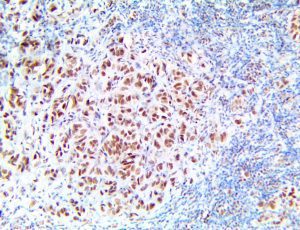

The first cytokines released are interleukin 1β (IL-1β) and tumor necrosis factor-α (TNF-α), which attract a variety of circulating white blood cells (WBCs) to the infection site, including neutrophils, monocytes, macrophages, and natural killer (NK) cells. This response, along with the antipathogenic chemicals released by these cells (i.e., complement), comprise the innate immune response. These cells directly attack the invading pathogen and also release additional cytokines, chief among them interleukin-1 and 6 (IL-6). IL-6 is essential for invoking the adaptive immune response, which calls T-cells, B-cells, and T helper (Th) cells to the infection site. IL-6 also stimulates further recruitment, proliferation and activation of macrophages.

It is the ICU physician who is most likely to witness one of the deadliest manifestations of the abnormal immunological response, the cytokine storm syndrome (CSS). This response is also referred to by some as the cytokine release syndrome (CRS). CSS is characterized by continuous activation and expansion of macrophage and lymphocyte populations, which secrete large amounts of cytokines, causing the cytokine storm. This massive cytokine release is akin to hemophagocytic lymphohistiocytosis (HLH) disease, a syndrome characterized by initial unchecked and persistent activation of cytotoxic T lymphocytes and NK cells.

Clinical and laboratory manifestations of HLH include fever, enlarged liver and/or spleen, neurologic dysfunction, coagulopathy, liver dysfunction, cytopenias (i.e., low levels of erythrocytes, leukocytes, and/or platelets), hypertriglyceridemia, hyperferritinemia, hemophagocytosis, and eventually diminished NK cell activity as the immune system becomes progressively paralyzed. HLH can be familial (primary HLH) or secondary to another disease process (sHLH), such as rheumatic disease, in which it is referred to as macrophage activation syndrome (MAS, characterized by elevated ferritin).